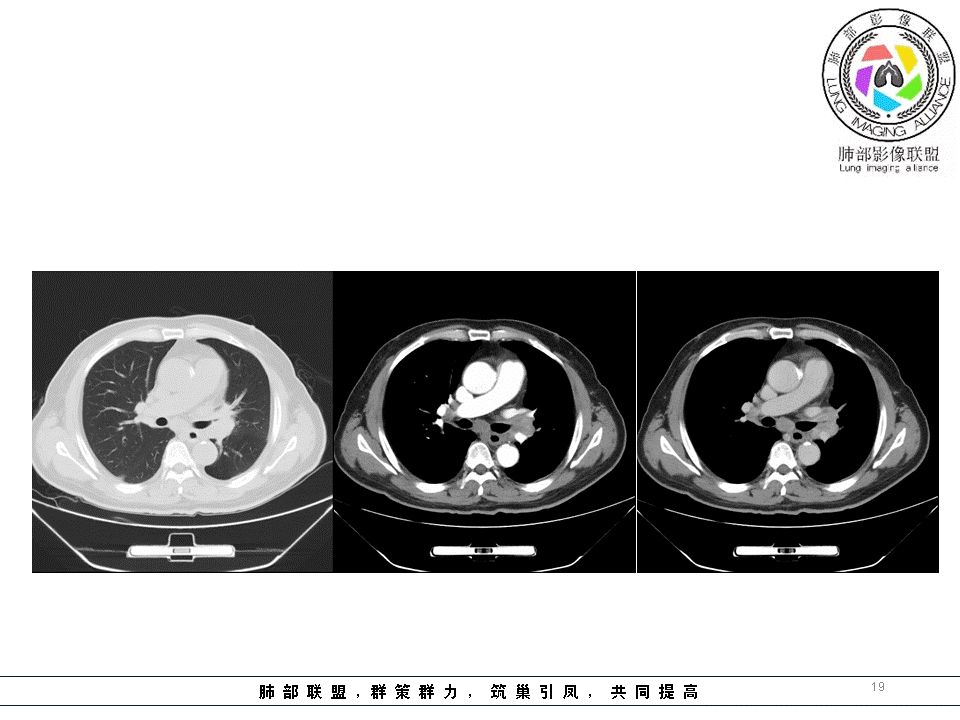

我们看影像,肺内有一些小斑点状高密度影,部分区域有气体潴留:

南边:我们现在影像上看的,也就是肺部小斑点,这些斑点,有些地方有气道储留的一个特点。

南边:但是我们看纵隔就多发的肿大淋巴结,部分融合成团。